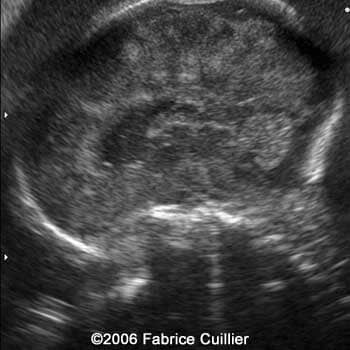

Left image: Left parasagittal view at 30 weeks showing anterior parasagittal hyperechoic areas. Right image: Bilateral parasagittal view at 30 weeks

6

7